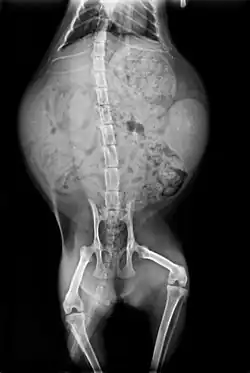

In this radiography of a pregnant cat, the skeletons of two fetuses are on the left and right of the uterus.

After mating, the female cleans her vulva thoroughly. If a male attempts to mate with her at this point, the female attacks him. After about 20 to 30 minutes, once the female is finished grooming, the cycle will repeat.[165] Because ovulation is not always triggered by a single mating, females may not be impregnated by the first male with which they mate.[166] Furthermore, cats are superfecund; that is, a female may mate with more than one male when she is in heat, with the result that different kittens in a litter may have different fathers.[165]

The morula forms 124 hours after conception. At 148 hours, early blastocysts form. At 10–12 days, implantation occurs.[167] The gestation of queens lasts between 64 and 67 days, with an average of 65 days.[162][168]